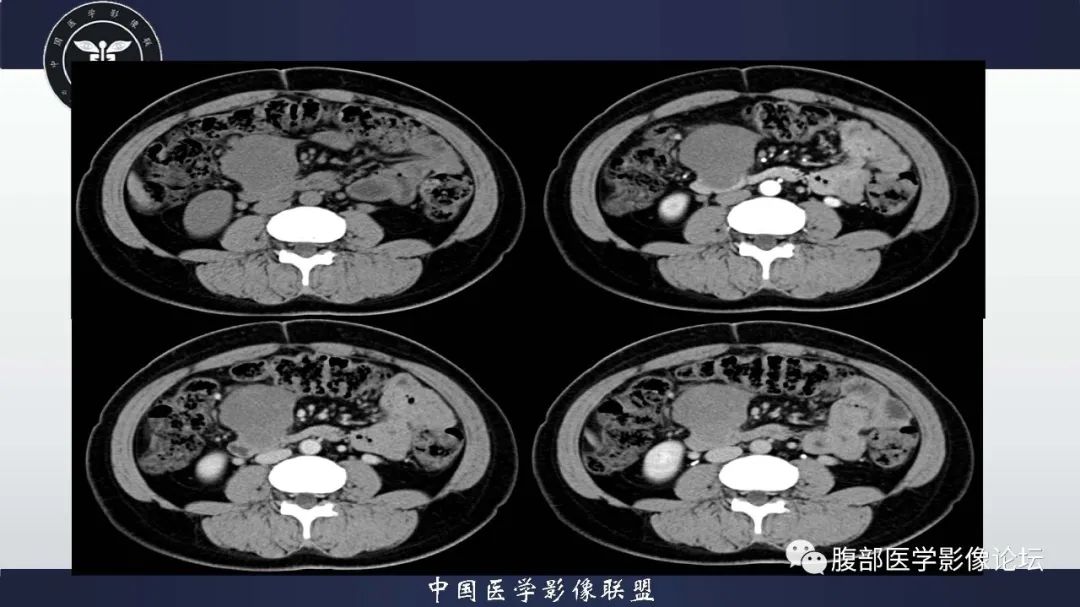

全身多发肿瘤--神经纤维瘤病

图片尺寸1332x701